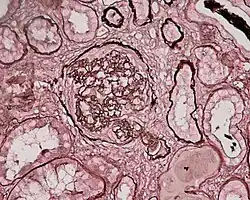

Photomicrograph of a kidney biopsy from a person with crescentic glomerulonephritis showing prominent fibrocellular crescent formation and moderate mesangial proliferation in a glomerulus. Hematoxylin and eosin stain. | |

Rapidly progressive glomerulonephritis, also known as crescentic GN, is characterised by a rapid, progressive deterioration in kidney function. People with rapidly progressive glomerulonephritis may present with a nephritic syndrome. In management, steroid therapy is sometimes used, although the prognosis remains poor.[9] Three main subtypes are recognised:[4]: 557–558

Histopathologically, the majority of glomeruli present "crescents". Formation of crescents is initiated by passage of fibrin into the Bowman space as a result of increased permeability of glomerular basement membrane. Fibrin stimulates the proliferation of endothelial cells of Bowman capsule, and an influx of monocytes. Rapid growing and fibrosis of crescents compresses the capillary loops and decreases the Bowman space, which leads to kidney failure within weeks or months.